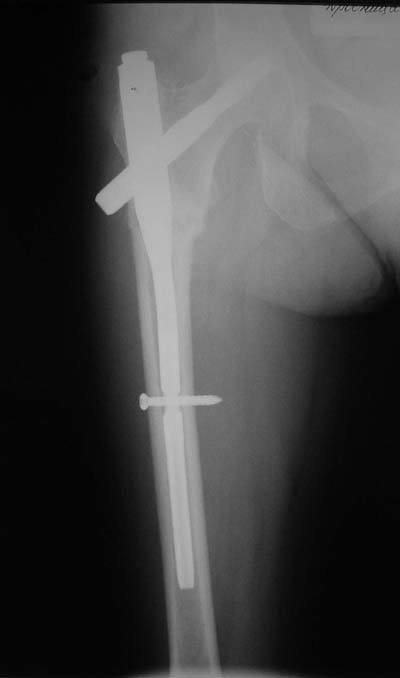

Да? Качество рентгенограмм конечно неочень, но ведь это нестабильный перелом 31.А2.2, не так ли?

Стремишься? А что мешает вообще не использовать короткие штифты?

Не думаю так. см вложение.